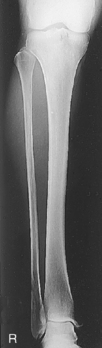

• Include ≈3 cm (1-1.5″) minimum beyond knee and ankle joints considering divergent rays

• Supine, or seated on table, with leg extended and centered to CR and midline of table or IR

• Rotate leg slightly inward as needed to place knee and leg into a true AP. Center IR to CR.